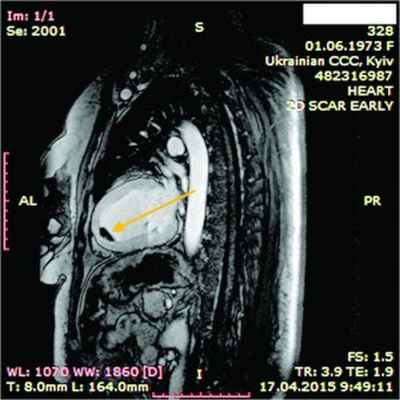

Рис. 7. Динамическая томография, боковая проекция с контрастированием эндокарда (1) и тромба ПЖ (2)

Рис. 8. Динамическая томография, поперечная проекция с контрастированием полостей и тромба в ПЖ (1), гидроперикарда по всем стенкам (2)

Рис. 9. Динамическая томография, поперечная проекция с контрастированными полостями и стенками – неравномерное утолщение миокарда желудочков (1) с двумя апикальными тромбами (2)

Рис. 10. Динамическая томография, боковая проекция с контрастированием полостей и стенок – апикальный тромб ЛЖ

Рис. 11. Динамическая томография, косая проекция с контрастированием полостей и стенок – апикальные тромбы ЛЖ

В ходе серии динамических МРТ с контрастированием (рис. 7-11) выявлены массивные пристеночные тромботические наслоения в ПЖ, апикальный тромб ЛЖ.